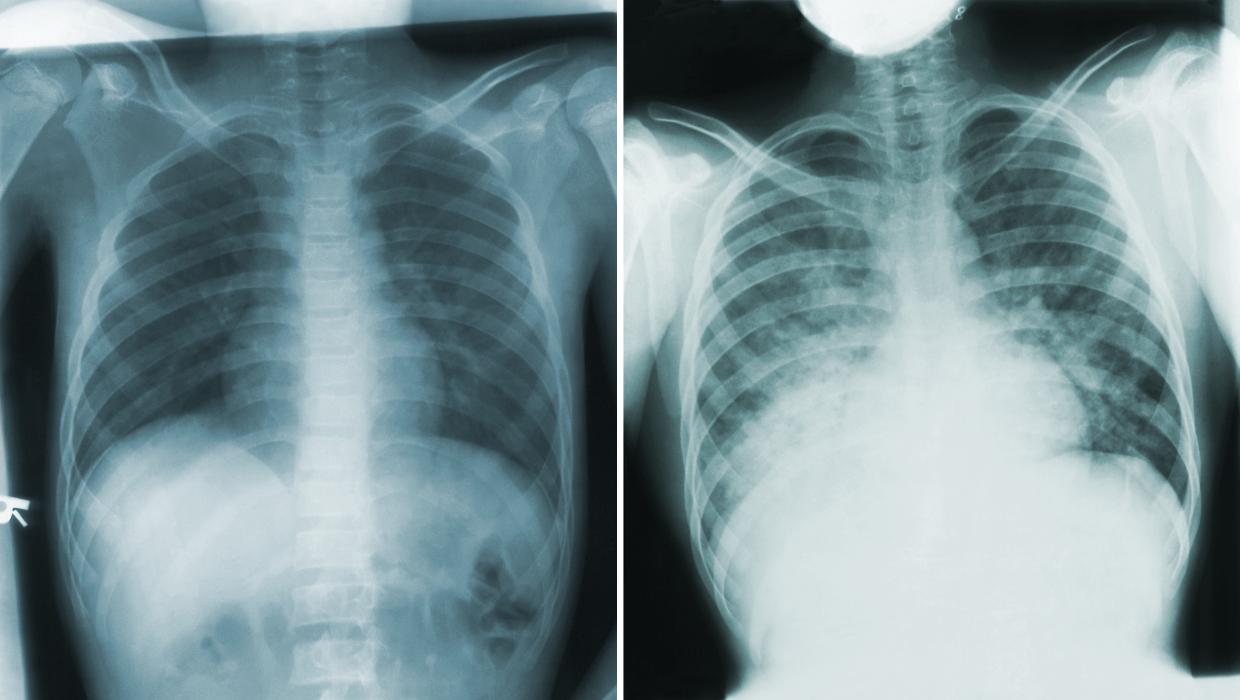

When the diagnosis of post-viral asthma was made, confusion continued. The physician prescribed albuterol, but Porter, familiar with the medication’s international name, recognized it as salbutamol. This moment revealed a deeper issue: healthcare systems often speak in different dialects, not only in medication names but also in data formats. Names such as EMR, Shared Care Record (SCR), and Health Information Exchange (HIE) contribute to the fragmentation of information.

Porter noted that a standard like the International Patient Summary (IPS) could serve as a universal language for health data, potentially allowing his son’s asthma plan to follow him back to New Zealand seamlessly. Despite the thoroughness and care of the clinicians, the experience left him feeling the complexities of navigating payment. He was presented with an itemized bill that suggested an expectation of negotiation, a practice that is foreign to many healthcare systems worldwide.